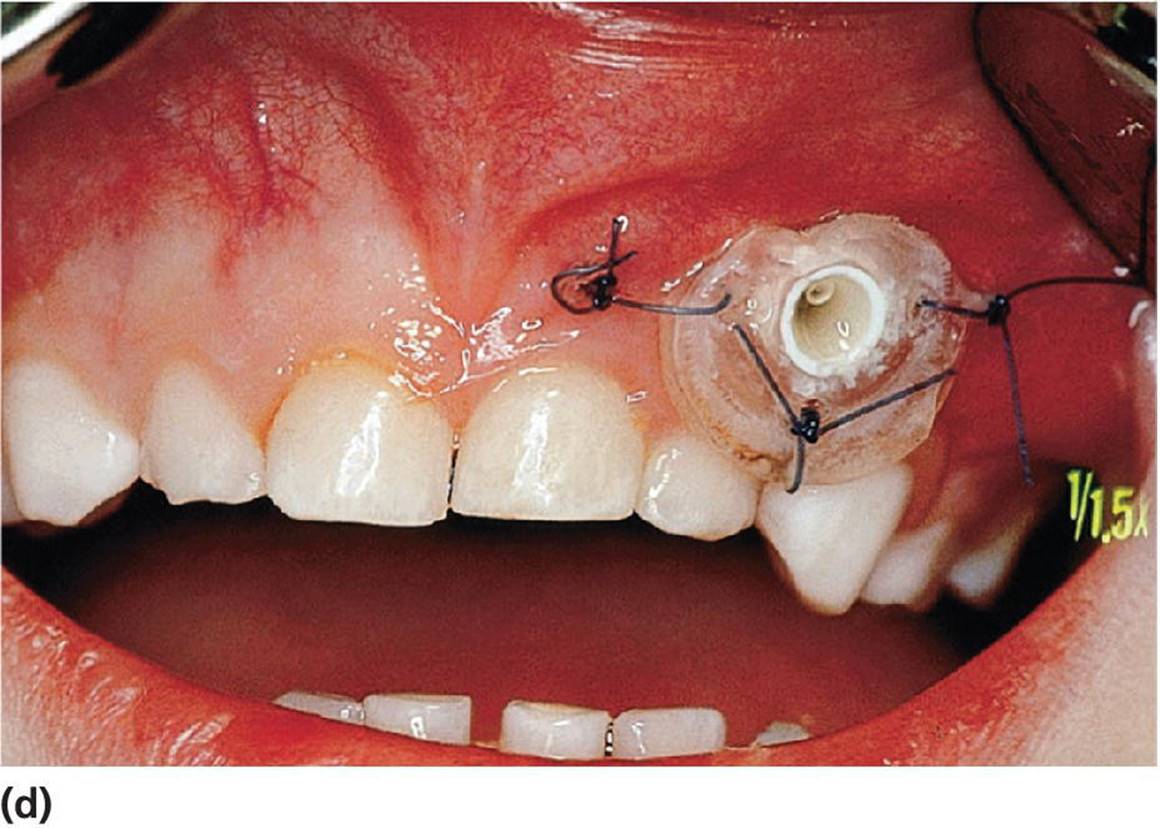

Figure 15.27 (a) Radiographs of upper right canine in palatinal ectopic position with risk for resorption of the permanent incisors. (b) After a palatinal muco‐periostal flap is raised and bone is removed the canine is exposed. (c) Brackets and gold chain are etched to the lingual surface of the canine. (d) The flap is sutured and the free end of the chain is temporarily fastened to a premolar. The contralateral canine was treated at the same session. The patient is now ready for the orthodontic treatment.